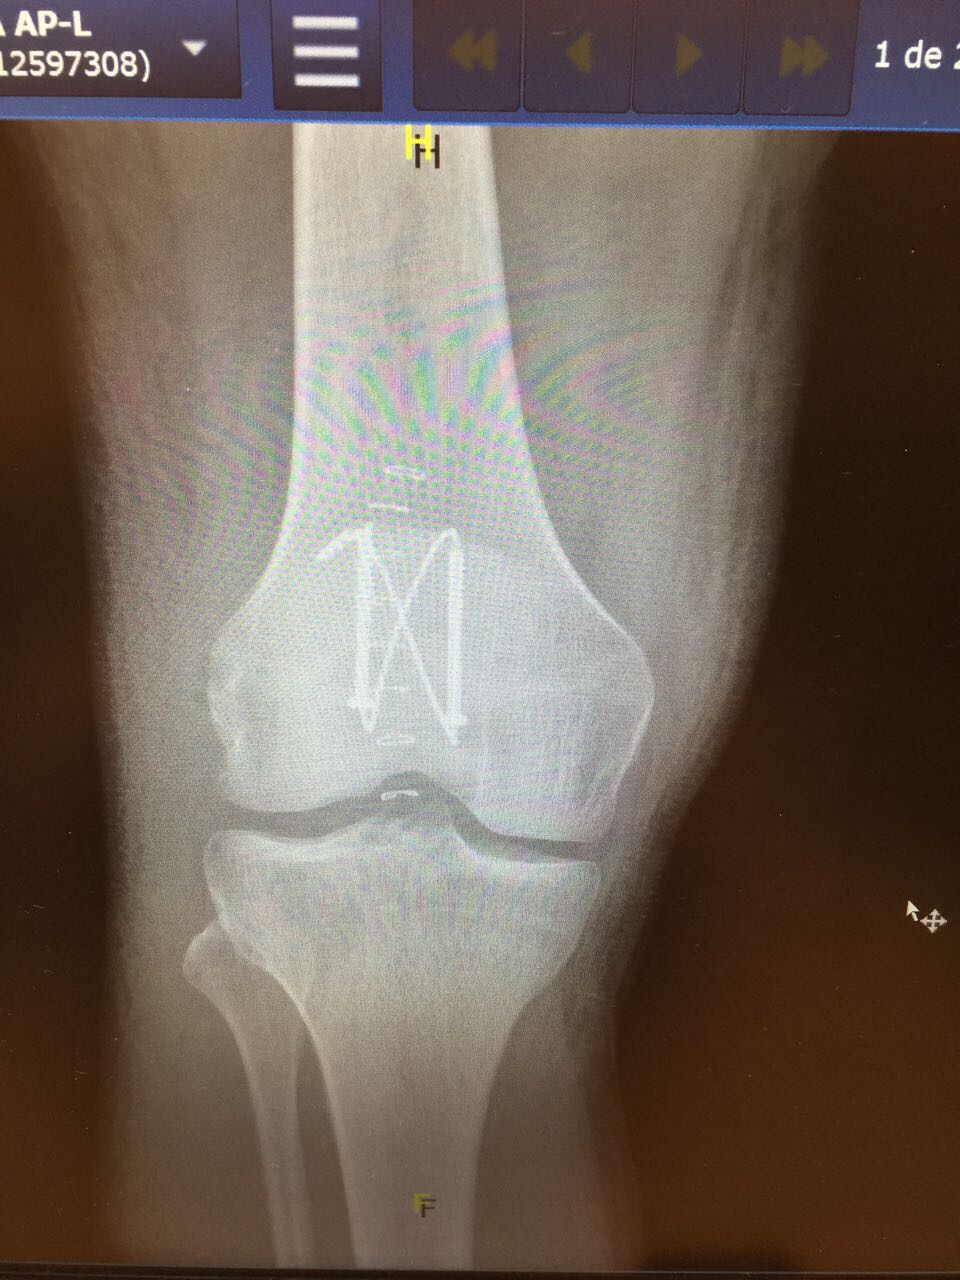

Under gårdagen var jag även på kontrollröntgen och konstaterade att allt såg bra ut och att skruvarna och ståltrådarna placerats som de skulle 🙂

Så tokigt kan det gå när man har otur och faller. Sjukt egentligen hur skör kroppen är när olyckan är framme. Har nog ramlat på skridskor ett hundratal gånger tidigare, men att hela min knäskåla skulle krossas, det är bra mycket otur det. Det kommer bli en lång väg tillbaka och sommaren blir ju långt ifrån vad jag planerat. Kommer inte kunna bli nått spring på akuten då jag kommer vara fast med kryckor och en gradreglerande skena runt benet de första 6 veckorna. Nu är den inställd på 0-30 grader och efter 6 veckor ska jag successivt ha tagit mig upp till 90 grader och kunna bli av med skenan. Sen kommer det dröja ytterligare en tid innan jag kan gå normalt. Får räkna med totalt 6 månaders rehabilitering. Så något maraton i Berlin i september som planerat blir det ju inte 😦